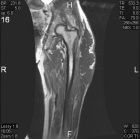

86 year old male with nontender, enlarging left thigh mass

Zoom image: Radiological image Radiological image.